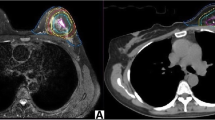

The TB delineation of CT and all MRI sequences was entirely performed from only a single modality by an experienced radiation oncologist to avoid inter-observer variation. Meanwhile, it was verified by another oncologist according to the criterion of the Radiation Therapy Oncology Group (RTOG) [9]. The whole breast is outlined on the CT to calculate the volume. The clips, seroma, and surgical scars were applied to guide the CT-based contours for CTVs, while the tumor as visualized on MRI was defined as the standard gross target volume (GTV) for MRI-based delineations. The target volume contours (CTV-CT and GTV-T1, GTV-T2, GTV-T2-SPAIR, GTV-DWI, GTV-dyn-eTHRIVE, and GTV-sdyn-eTHRIVE) were performed on the axial slices; simultaneously, sagittally and coronally reconstructed images could be used to verify the delineations. The corresponding CTV-MRI was obtained respectively by extrapolating 1.0 cm of the GTV-MRI based on the MRI sequence according to the surgeon’s clinical experience and the expert consensus (Fig. 1). And various PTVs were defined as unified margins of 15 mm expanded based on the corresponding TBs, and trimmed 5 mm from the skin to the breast-chest wall interface (Fig. 2). Each MRI sequence was scheduled to register to CT, respectively. The consistence index (CI) and dice coefficient (DC) of CTVs and PTVs between CT and each MRI sequence were measured to quantify the extent of overlap of two volumes; the geographical miss index (GMI) and normal tissue index (NTI) were considered as non-conformity parameters between different imaging modalities. DC = 1 represents perfect overlap, while DC = 0 represents no overlap. The specific calculation of these parameters is shown in Fig. 3. The cavity visualization score (CVS) of CT was also evaluated. CVS = 1 means that the cavity was not visualized; CVS = 2 means that the cavity was visualized with indistinct margins; CVS = 3 means that the cavity was visualized with some distinct margins and heterogeneous appearance; CVS = 4 means that the cavity had distinct margins in the majority of LC with mild heterogeneity; and CVS = 5 means that the cavity has distinct margins in the entire LC with a homogeneous appearance [21].